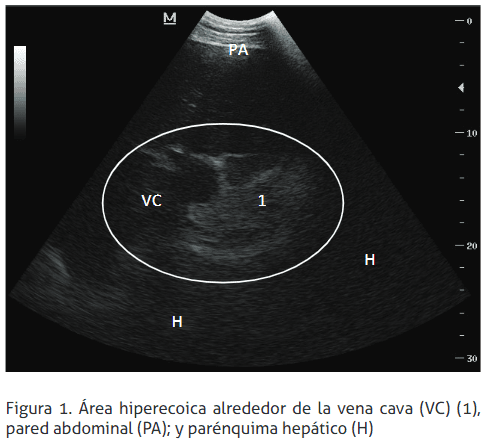

En el flanco derecho, en la evaluación hepática, se observa áreas extensas de ecogenicidad aumentada alrededor de vena cava. Esto, según Braun (2009b), es compatible con fibrosis o la formación de un absceso debido a los cambios estructurales circunscritos en el parénquima hepático (Figura 1). Además, las paredes de los vasos hepáticos se observan hiperecoicas, siendo sugestivo de un cuadro de lipidosis hepática (Braun 2009b; Imran etal. 2011). Se observa, también, marcada peritonitis a nivel de la pared del retículo y delrumen (Braun et al. 1993; Braun et al. 2013), con la formación de un espacio de 3,5 cm de distancia entre pared abdominal y pared de los órganos internos; en este espacio se observa distintos grados de ecogenicidad a lo largo de la evaluación de las paredes, sugiriendo alto contenido de exudados y transudados. Se determinó, además, gran cantidad de material fibrinopurulento diseminado en la cavidad (Figura 2).